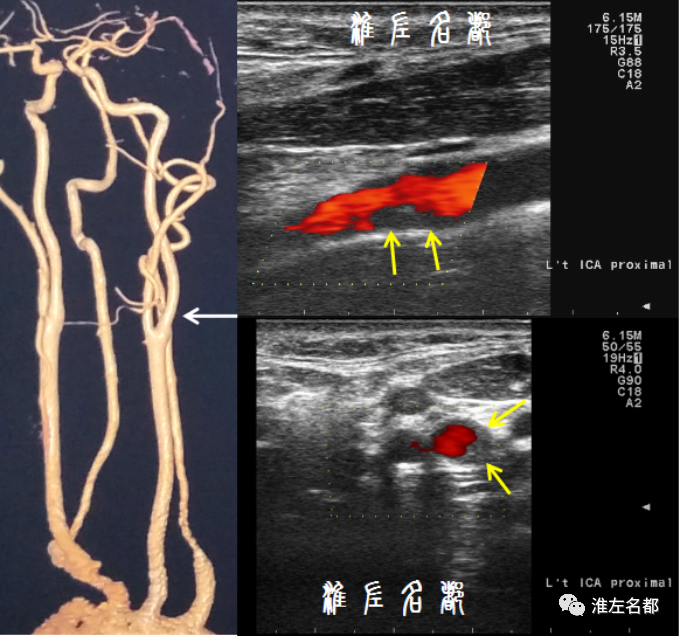

在脑血管病变领域,超声技术早就应用于颈动脉斑块评估,这是因为颈动脉管径相对粗大,位置表浅,有利于超声成像显示颈动脉斑块。此技术空间分辨率高,还能辨别不同斑块组织的回声特性;配合彩色血流技术或超声造影技术,可进一步得到较准确的斑块表面形态信息;结合测量,以及多普勒技术,能比较准确地判断管腔狭窄程度。不足之处在于,对操作和结果解读人员的专业素养要求极高,不可重复;可惜的是国内此领域的高水平从业者不多。

根据好发部位和特征性影像改变,颈部血管疾病通常能获得准确的病因诊断;另外,常规的超声技术和CTA技术即可获取颈动脉管壁异常信息,并足以指导临床决策。因而,在目前的颈部脑血管病变的临床实践中,除了个别情况(医学研究,疑难病因诊断,或颈动脉闭塞介入再通治疗术前评估等),管壁高分辨MRI技术并不是常规需求。